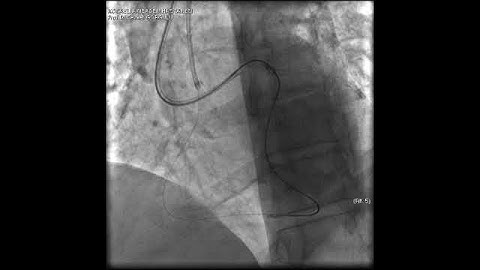

Aortic dissection and radial rupture during retrograde CTO PCI: Management of complications VİDEO 15